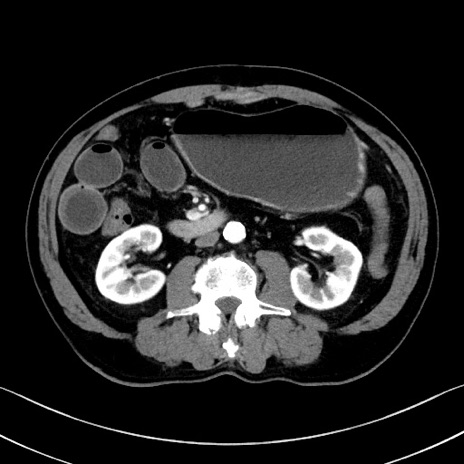

症例35(横断像)

【症例】70歳代 男性

【主訴】腹部膨満、嘔吐

【現病歴】昨日より腹部膨満感出現。本日増悪し、仙痛出現。嘔吐あり、受診。

【既往歴】糖尿病、胆摘後

【身体所見】BP 149/80mmHg、HR 74/min、BT 35.9℃、腹部:膨満、軟、圧痛なし。腸雑音減弱あり。上腹部正中切開瘢痕あり。

【データ】WBC 13500、CRP 1.72